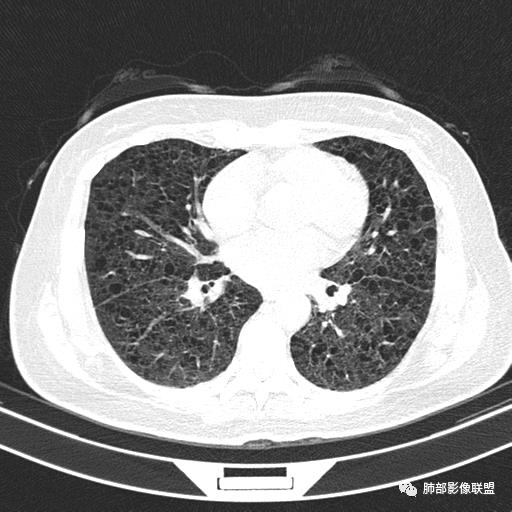

双肺弥漫囊腔,累及肋膈角,囊腔形态相对规则单一。

CT平扫示双肺弥漫分布大小不等囊状薄壁透光区,无内、中、外带分布差异,间质稍示增厚。拟LAM

中年女性育龄期妇女,咳嗽气喘,无吸烟史,有苯吸入史。影像:双肺弥漫均匀小囊腔,无明显分布优势,囊腔形态欠规则,壁薄,部分囊腔边缘血管征,伴双肺弥漫磨玻璃影,无结节,考虑lam,鉴别苯中毒肺损伤,囊腔多有分布优势,小叶中心分布为主,形态规整等

CT表现:双肺弥漫大小不等的薄壁囊腔,囊壁<2mm,外形规则,血管影多位于囊腔周围,囊腔之间肺组织正常,随着疾病进展到晚期,囊腔变大、增多,不可胜数,囊腔可融合成较大的囊,与肺气肿相似,形成间质性肺纤维化。部分病例可出现结节影。